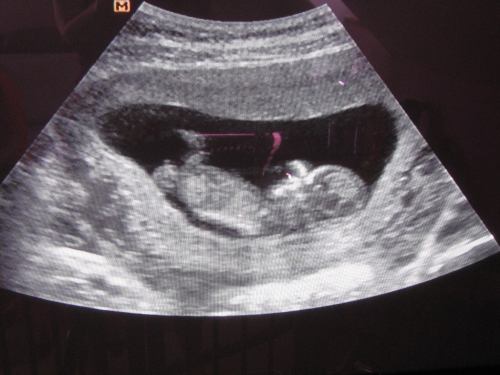

Kedden voltunk a kaáliba uh vizsgálaton, minden rendben van, így indulhat a kezelés!